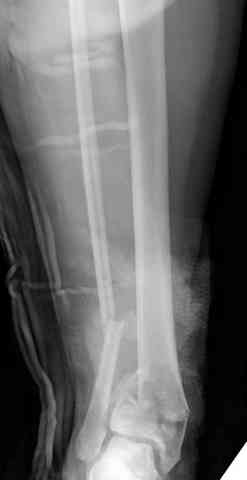

Снова приветствую вас, коллеги. К моменту вступления в обсуждение аксакалов, операция была, увы, выполнена(31.10.07.) Начали с доступа к наружной лодыжке, произвели ее фиксацию спицами, развернули кусок заднего края, наложили дистрактор, затем произвели дистракцию, фиксацию спицами дистального эпиметафиза б/бк,Рентгено-контроль. синтез наружной лодыжки 1/3пластиной. из двух коротких разрезов сформирован канал под медиальную тибиальную пластину LCP. Края ран ушиты без натяжения. Прочувствовать жесткость фиксации винтами с угловой стабильностью не удалось, поэтому дистрактор оставлен на энное время.

На представленных R-снимках не окончательный вид после остеосинтеза. Дистальная опора давила на стопу, пришлось ее сместить проксимально, в рез-те чего, она закрыла щель сустава, последние снимки не информативны.

Дистальные винты как-то чуть не все идут не в дистальные отломки, а в зону перелома. И действительно, присоединяюсь к вопросу Якова - в диафизе так и оставили 1 винт?